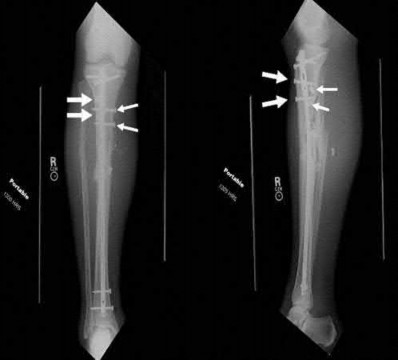

A 64-year-old woman is thrown off a horse, sustaining the injury shown in Figures A and B. She undergoes surgical fixation as seen in Figures C through E. What is the most commonly reported complication of this procedure?

The patient in the scenario has a 2-part proximal humerus fracture treated with a locking plate as seen in Figures A-E. The most common complication with the use of this implant is screw penetration. The terms screw cut out and penetration are often used interchangeably in the literature with cut out appearing more frequently in reports regarding intertrochanteric fractures.

Owsley et al retrospectively reviewed 53 proximal humerus fractures treated with locking plates and the same post-operative protocol. The most common complication was screw cut out or penetration, followed by varus displacement. They concluded that 3 and 4-part fractures in patients over 60 years have a higher incidence of failure.

Agudelo et al retrospectively reviewed 153 patients at a level-one trauma center treated with proximal humerus locking plates, investigating modes of failure for the implant. They determined that varus malreduction (head-shaft angle